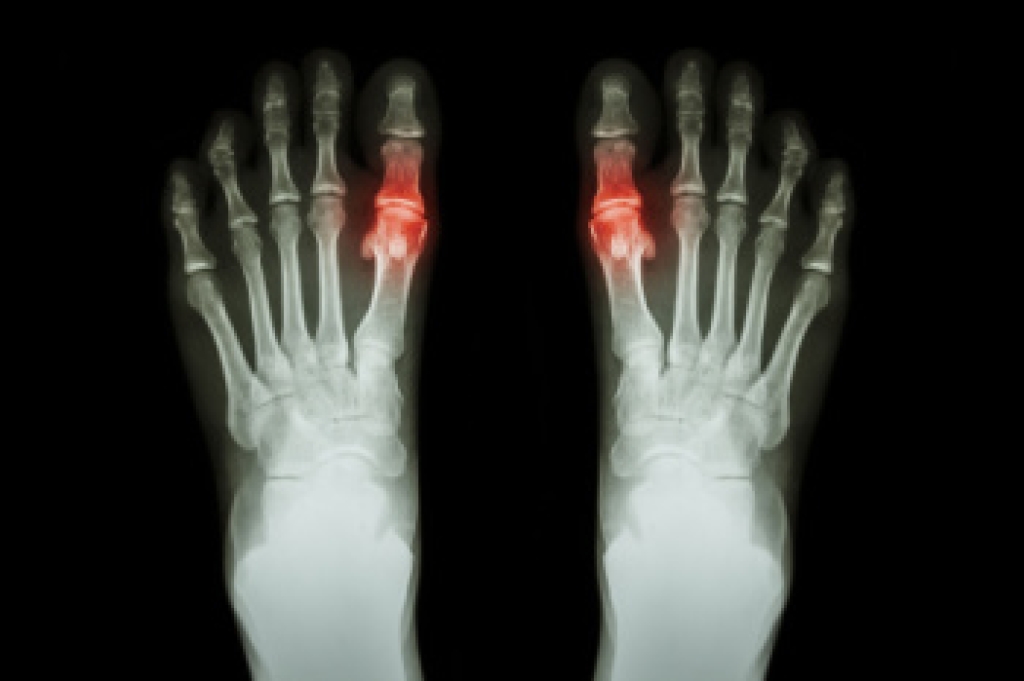

Tarsal tunnel syndrome, which can also be called tibial nerve dysfunction, is an uncommon condition of misfiring peripheral nerves in the foot. The tibial nerve is the peripheral nerve in the leg responsible for sensation and movement of the foot and calf muscles. In tarsal tunnel syndrome, the tibial nerve is damaged, causing problems with movement and feeling in the foot of the affected leg.

A physical exam of the leg can help identify the presence of tarsal tunnel syndrome. Medical tests, such as a nerve biopsy, are also used to diagnose the condition. Patients may receive physical therapy and prescriptive medication. In extreme cases, some may require surgery.